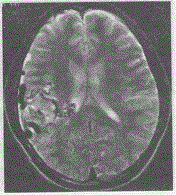

问题 男,17岁,右颞部胀痛,MRI如图所示,最可能的诊断是

选项 A.脑炎 B.血管畸形 C.动脉瘤 D.脑膜瘤 E.脑出血

答案 B